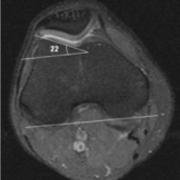

This patient's trochlear inclination angle is 22 degrees, which is in the normal range.

The lateral trochlear inclination angle quantifies the degree of any trochlear dysplasia or flattening of the groove of the femur where the patella runs. Page updated October 2023 by Dr Sheila Strover (Clinical Editor)

The LTI is an MRI calculation of the angle between the lateral edge of the femoral notch and the posterior edge of the femur at the level of the femoral epicondyles.

To measure the angle, one draws the line along of the wall of the trochlear groove underneath the cartilage layer. Then a line is drawn at the back of the two condyles - from it a parallel line can be extrapolated to meet the first one, to make it easier to see the angle.

If the LTI is 20-22 degrees the slope of the wall of the trochlea is considered normal. However, if it is below 11 degrees it is considered dysplastic. For some severely affected people it can be even zero or less. A flattened dysplastic trochlea makes it easier for a patella to sublux or to dislocate, and thus this angle is important to calculate when assessing the causes of such patellar instability.